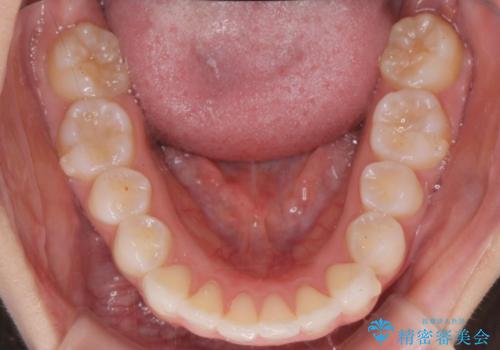

前歯のがたつき気になる。インビザラインモデレート

- 前歯のがたつきが気になるとの事で来院。

噛み合わせを確認したところ上の歯が全体的に前にある状態でした。

患者様は2のプランを選ばれたのでインビザラインモデレートで治療を行いました。

ガタつきがなくなり満足して頂けました。

矯正後は補綴装置をつけないと後戻りしてしまう可能性があるので

補綴装置をしっかりと装着する必要があります。